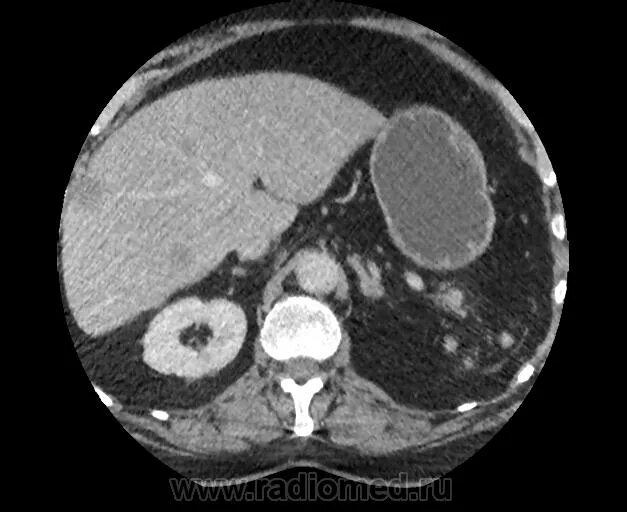

Кт обп омт с контрастированием